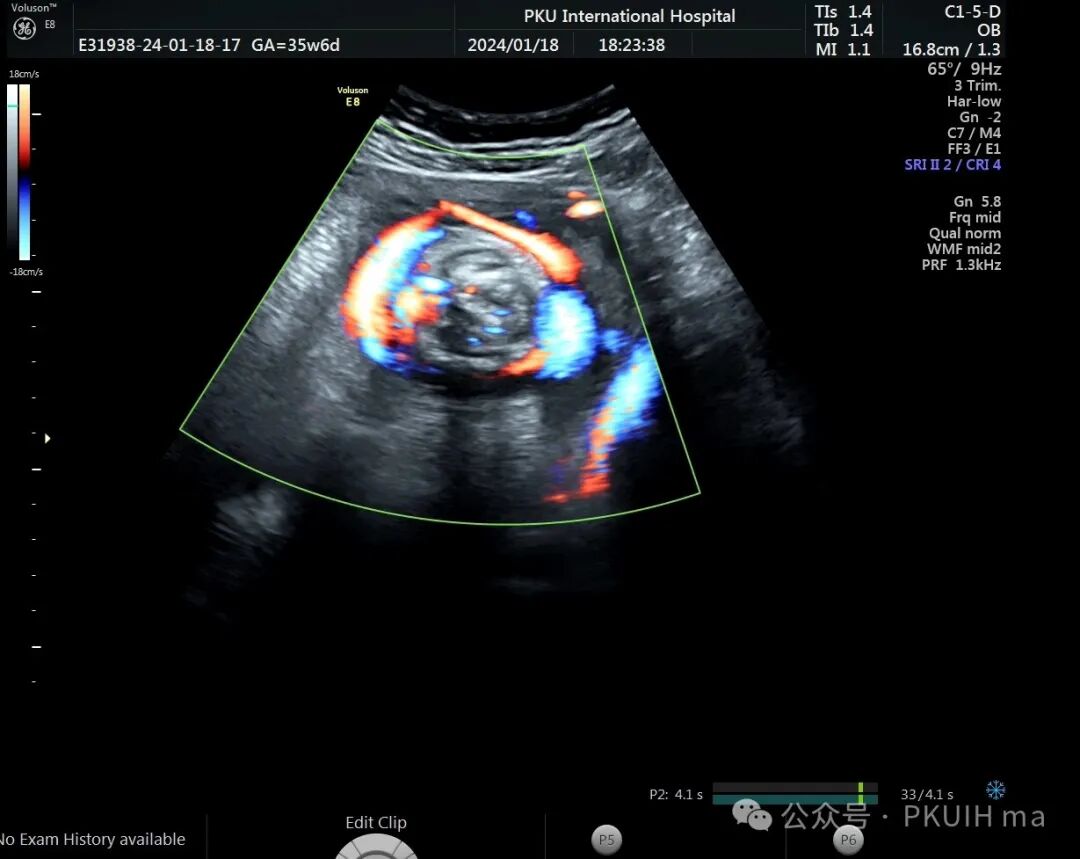

前两天碰到一孕妇胎动减少来诊,孕妇自述下午两点开始发现胎儿无明显胎动,吃了甜的食物和改变姿势还是不怎么动,随于下午六点左右来诊。超声发现胎儿绕颈两周以上且绕的较紧,检查中发现胎儿心率快,胎儿无明显胎动,绕颈处脐动脉血流加速时间延长,胎儿大脑中动脉阻力低,反复测量两侧大脑中动脉阻力均低。胎心监护也不好,随后产科采取紧急剖宫产。

脐带绕颈两周以上,绕的特别紧,感觉脖子都被勒细了,脐带与皮肤之间无任何空隙。绕颈处血流加速时间延长,说明可能存在交锁并出现了脐动脉局部狭窄